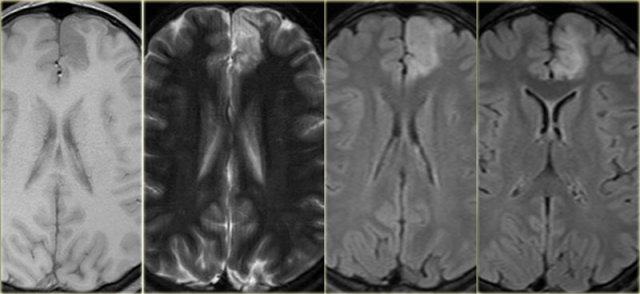

Các hình ảnh cho thấy loạn sản vỏ não khu trú điển hình.

Có hình ảnh dày vỏ não và mờ ranh giới chất xám/chất trắng trên chuỗi xung T1W (bên trái).

Ảnh FLAIR bên phải cho thấy tăng tín hiệu vùng dưới vỏ.

Các hình ảnh cho thấy bất thường tín hiệu vỏ não và dưới vỏ trên chuỗi xung T2W và FLAIR ở thùy thái dương trái, phù hợp với loạn sản vỏ não khu trú.

Lưu ý hình ảnh hồi hải mã tăng tín hiệu T2/FLAIR kèm teo nhỏ là hậu quả của xơ cứng thùy thái dương giữa, tức là bệnh lý kép.

Ảnh chuỗi xung T1W, T2W và FLAIR mặt phẳng axial của bệnh nhân nam 15 tuổi bị động kinh.

Lưu ý hình ảnh dày và tăng tín hiệu vỏ não hồi trán trên bên trái.

Ảnh FLAIR cũng cho thấy tăng tín hiệu ở chất trắng dưới vỏ.

Các dấu hiệu này điển hình cho loạn sản vỏ não khu trú.